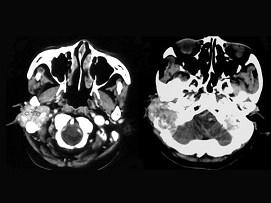

女,56岁,右侧中耳术后发现右外耳道新生物一年,PE:右外耳道内段被新生物充满,CT如图所示,应诊断为 ( )A、听神经瘤B、中耳结核...